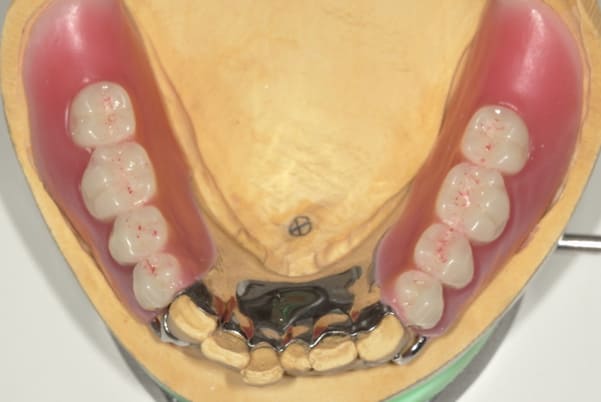

完成前に適合や見た目のチェック

完成前に適合や見た目のチェックでは、咬む力で義歯がたわみ、残りの歯に負担がかからないよう、見えない内側は、金属を用い、強度を増し、また金属のため薄くすることで違和感をなくす設計とし、完成前に試し合わせを行い、装着感、審美性を確認しました。